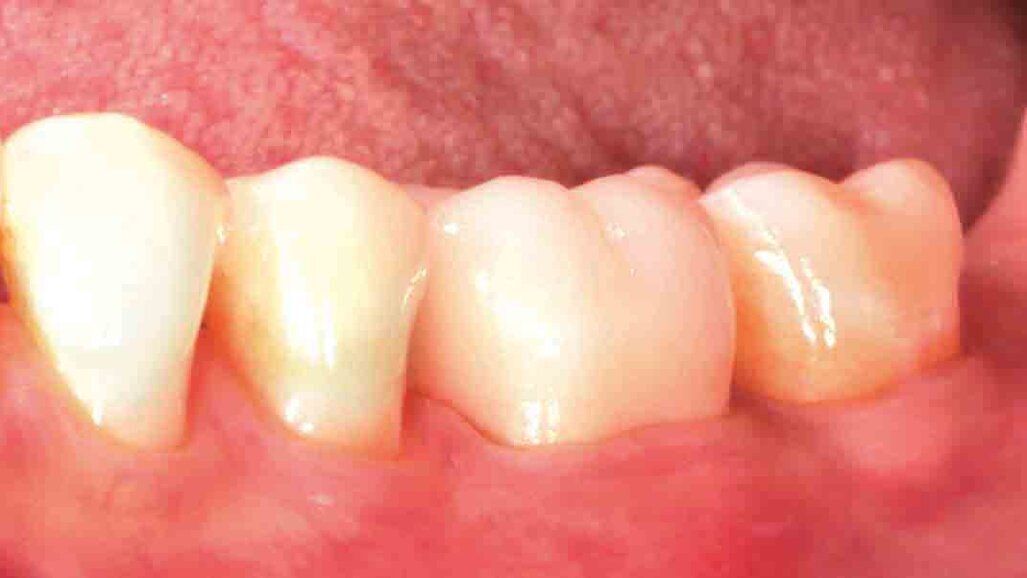

Fig. 1: Initial situation. The failed composite restoration covering a large part of the left mandibular first molar’s occlusal surface needs to be replaced.

Fig. 2: Due to the size of the restoration, the amount of remaining tooth structure might not be sufficient to ensure the required stability for a direct composite restoration.